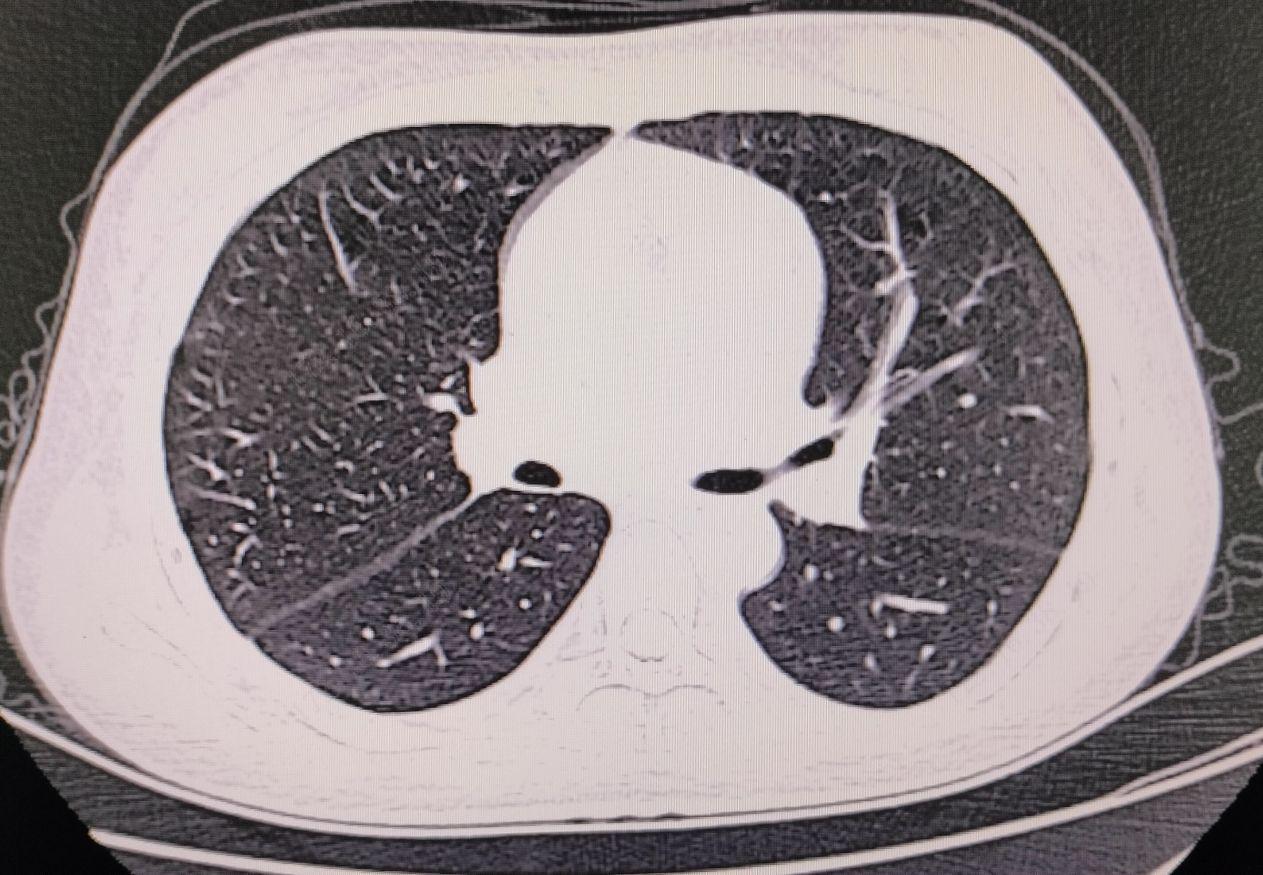

血常规:红细胞3.45*10^12/L,血红蛋白93g/L,红细胞压积27.3%,血小板129*10^9/L。尿常规:红细胞776个/uL,蛋白2+。凝血功能正常。生化:总蛋白82.3g/L,清蛋白31,尿微量蛋白3535.1mg/L。铁蛋白测定196ng/ml,尿酸459.9umol/L,钙2.05mmol/l,C反应蛋白11.6mg/L,抗核抗体提物示:抗Sm抗体阳性,Scl-70弱阳性,重组Ro-52阳性,SS-B阳性,双链DNA阳性,核小体阳性,组蛋白阳性,干燥综合征相关抗原A/Ro60阳性,抗核抗体核颗粒型阳性(1:320)。大便常规、肾功能、心肌酶谱、血糖、血脂、肿瘤标功三项、乙肝五项、输血前三项未见异常,心电图示:正常范围心电图。胸部CT示:1、两肺少许小结节,拟增殖灶,2、心包、双侧胸腔少量积液。